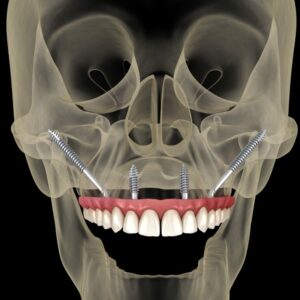

Tooth Replacement Options After Loss

After a tooth is lost, common replacements include a dental implant and crown, a fixed bridge that uses neighboring teeth for support, a removable partial denture, or a full denture when many teeth are missing. The right choice depends on your goals, oral health, bone support, and the location of the gap.

A back molar is extracted after a deep crack. An implant replaces the root and holds a crown; this avoids shaping the adjacent teeth and helps preserve biting support. For full arches, implant overdentures can add stability compared with traditional dentures. Selection also depends on your health, bone quality, and the tooth loss causes involved. Planning the number and position of implants, as well as how your bite loads them, influences long‑term success [9].

Fixed bridges fill a single‑tooth space by crowning the teeth on either side and suspending a false tooth between them. This can be a good option when those neighbors already need crowns, or when implant placement is not advisable. Removable partial dentures use clasps and a base to replace several missing teeth and are often a lower‑invasiveness solution, though they require daily removal and cleaning. If you are weighing a single‑tooth gap, this comparison can help you compare bridges and implants. When a compromised tooth can be treated predictably, preserving it may be cost‑effective compared with extraction and implant placement in some severe periodontal cases [10].

Timing matters too. In certain cases, early replacement helps maintain gum shape and function; in others, short healing periods or bone grafting are recommended first. Any option benefits from steady home care and regular checks to protect the surrounding teeth and gums. If you are unsure where to start, a focused exam and bite assessment will clarify which path best supports chewing, speech, and long‑term comfort. Thoughtful planning helps you chew comfortably and smile with confidence.